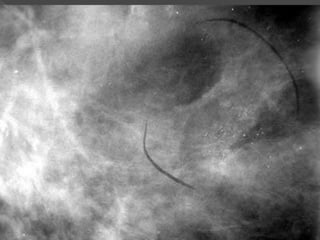

 81 AÑOS

 MAMOGRAFIA CONTROL

 MICROCALCIFICACIONES

 ALTO GRADO DCIS

 41 mm

 COMEDO NECROSIS

 MARGENES MENORES DE 5 mm

S. Ralon

USC/VNPI 9

EXCISION MAS RADIOTERAPIA

TAMOXIFEN

O

MASTECTOMIA SI CONTRAINDICACIONES

DE RADIO

Dr. Ralon